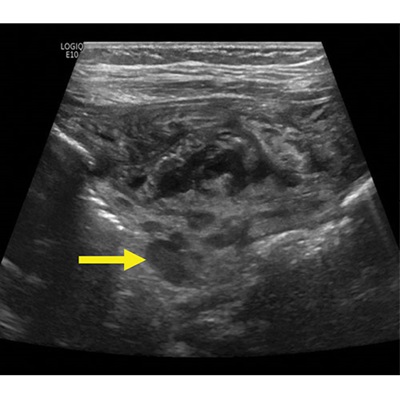

7-month-old male with Pediatric Inflammatory Multisystem Syndrome Temporally associated with SARS-CoV-2 (PIMS-TS). Non-contrast ultrasound image of the right iliac fossa in the transverse plane showing extensive inflammatory change with abnormal lymph nodes in the right iliac fossa (arrow).

Meshaka et al, Radiology 2022; ©️RSNA 2022